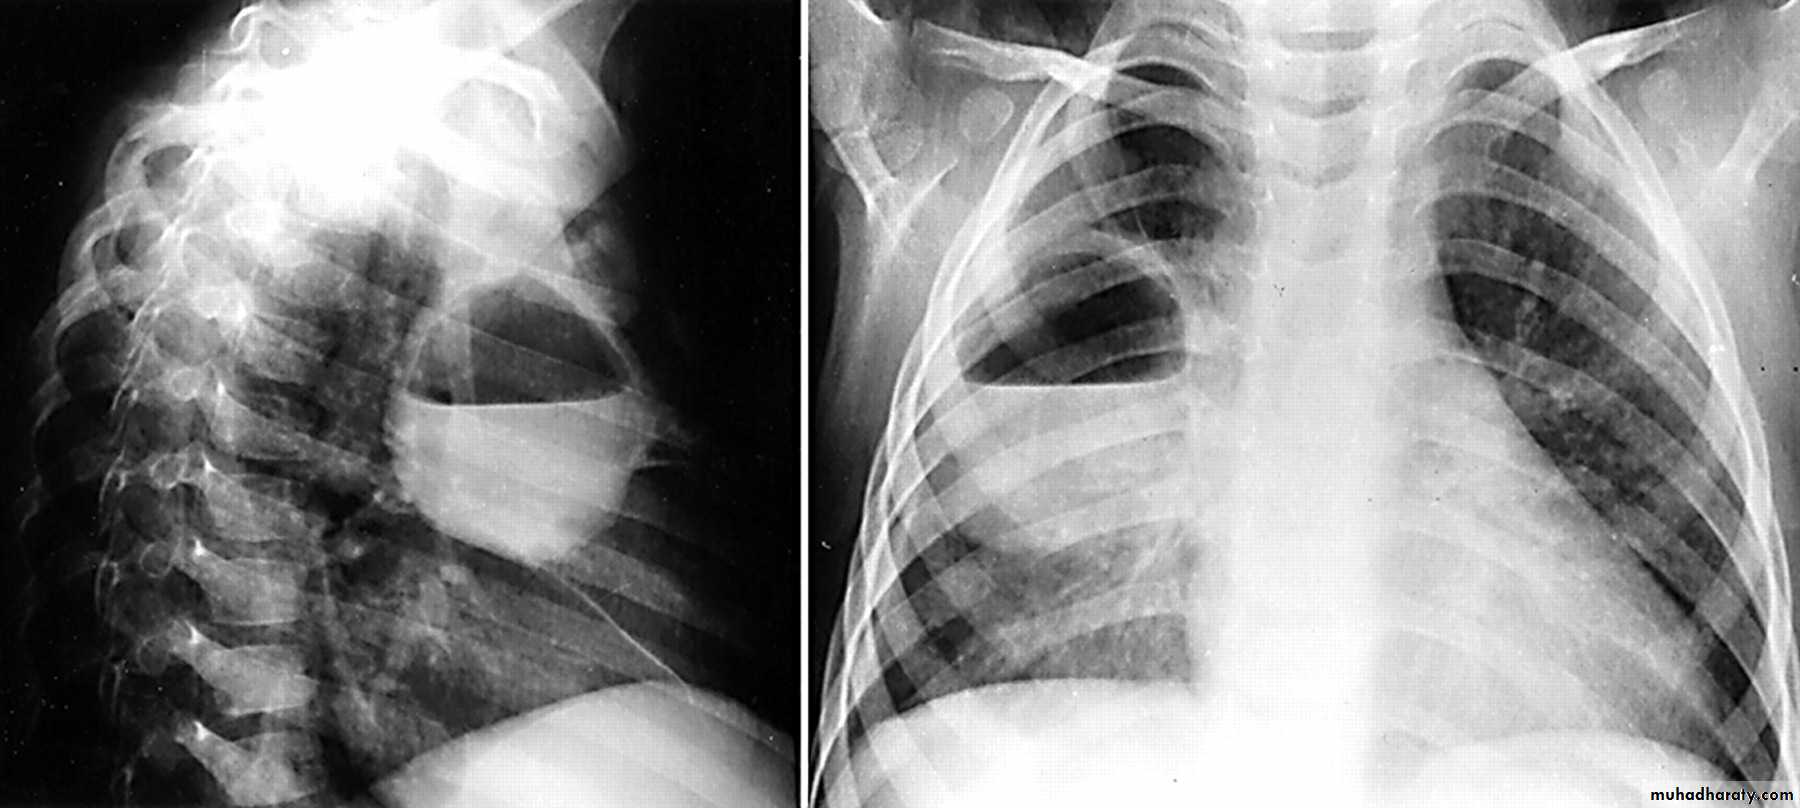

What is the main difference between 2 films ??? What is the shape of each one ??? A. B.

44.A.RT middle lobe consolidation

B.RT middle lobe collapse